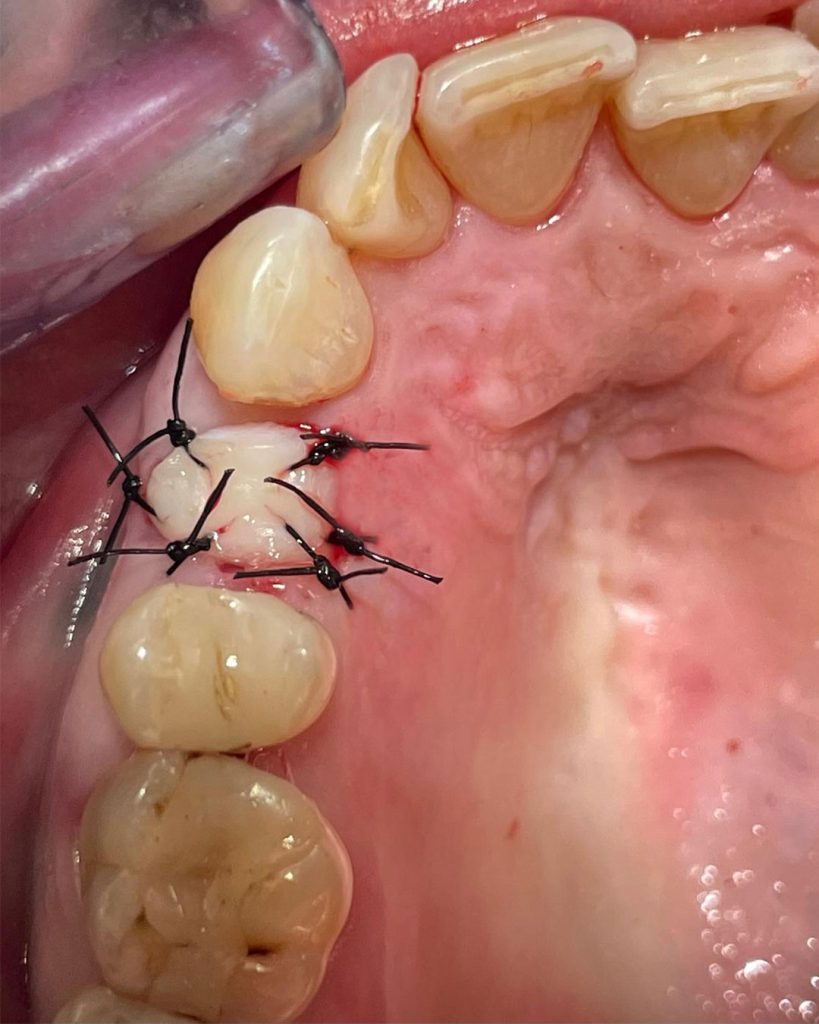

In questo intervento è stata tolta la radice e poi inserito contestualmente l’impianto. A copertura, per una migliore guarigione, è stato prelevato un coriandolo di tessuto cheratinizzato dalla zona retromolare con un mucotomo circolare e poi innestato sopra l’impianto in modo da proteggerlo.

Nelle immagini è possibile osservare la radiografia iniziale, la radiografia post-operatoria e la TAC pre-chirurgica con la progettazione dell’impianto.